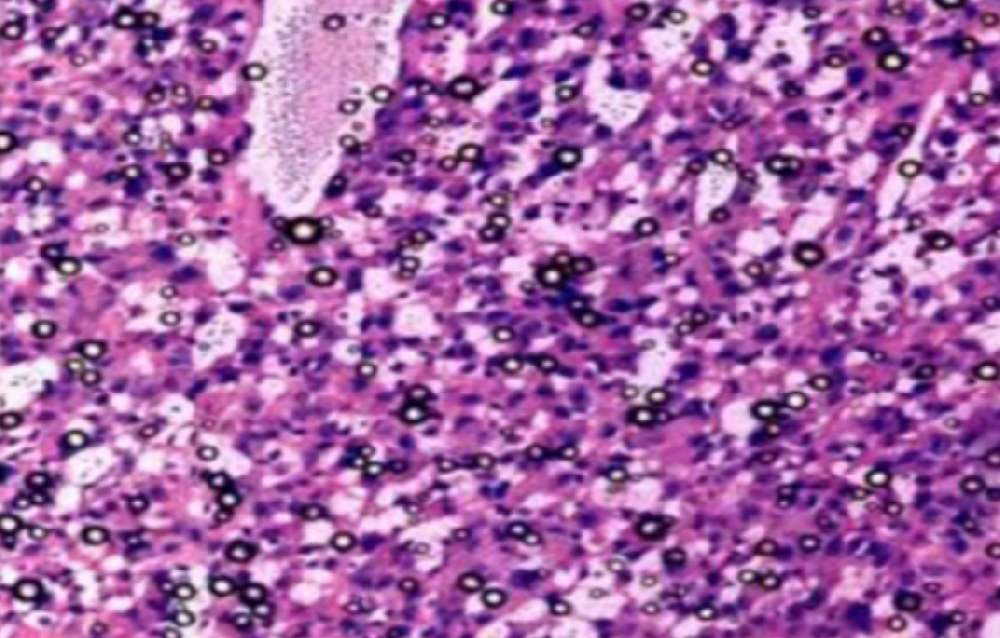

新疆组织病理学实验

实验外包——搞定这几点,轻松做出 "顶配 "免疫组化切片!!

一张高质量的免疫组化染色切片为正确判断染色结果提供了良好的基础和前提。由于免疫组化染色过程中存在很多步骤或环节,每一个步骤或环节都可能影响到染色的最终结果。虽然···